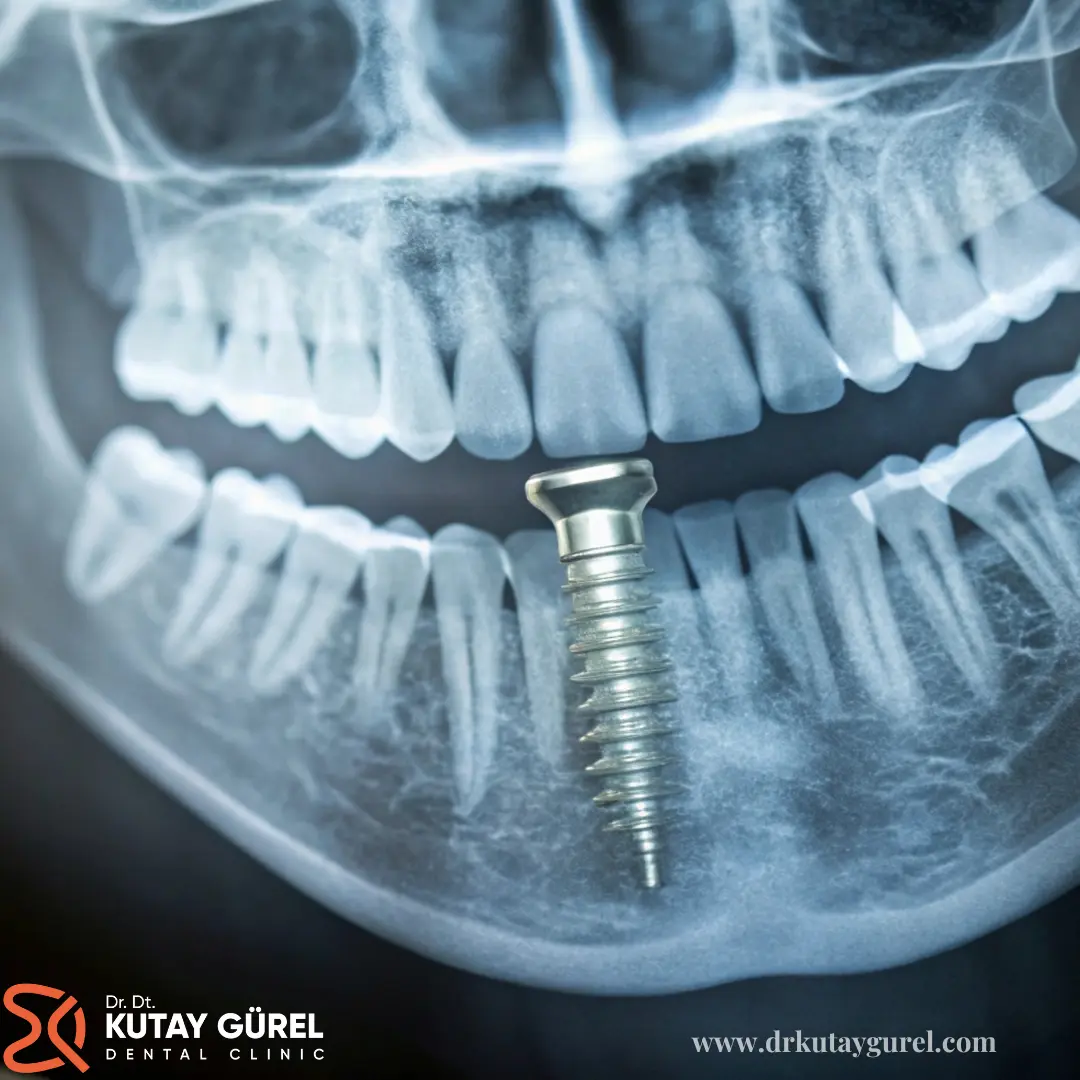

All on 4 implant tedavisi, özellikle dişsiz hastalar arasında yaygın olarak tercih edilen ve başarısı kanıtlanmış bir uygulamadır. Bu tekniğe göre, her bir eksik diş için ayrı ayrı implant yerine, dört adet implant farklı açılarda yerleştirilir ve üzerlerine tüm dişler bir arada takılır.

• Dental implant yerleştirme: Doğru açı ve konumda, çene kemiğinin anatomik yapısına uygun şekilde 4 adet dental implant yerleştirilir. Ön bölümdeki implantlar 90 derece, arka bölümdeki implantlar ise 45 derece açıyla yerleştirilir.

Bu tedavide dört adet implant, alt veya üst çene kemiklerinin uygun bölgelerine açılı olarak yerleştirilir. All on 4 tedavisinin başarısının yüksek olmasının nedenlerinden biri, çene kemiğinin tamamının değil, yalnızca bir kısmının kullanılabilmesidir.